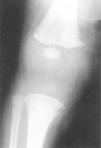

Exámenes complementarios: anemia normocrómica y trombocitopenia (26.000/μl). Elevación de GOT, GPT y GGT; el resto de la bioquímica, normal. Elemental de orina, normal. Serología de sífilis: RPR positivo (título, 1/128) y microaglutinación de Treponema pallidum (TPHA) positiva (1/2.560). Otras serologías, incluido VIH, negativas. Análisis de LCR normal, con VDRL negativo. Ecografía: hepatoesplenomegalia y nefromegalia bilateral. Radiología ósea: lesiones metafisarias en muñecas y rodillas con bandas de rarefacción ósea y pequeñas fracturas en los ángulos metafisarios, con reabsorción ósea en ambas metáfisis tibiales (signo de Winberger) (fig. 2).